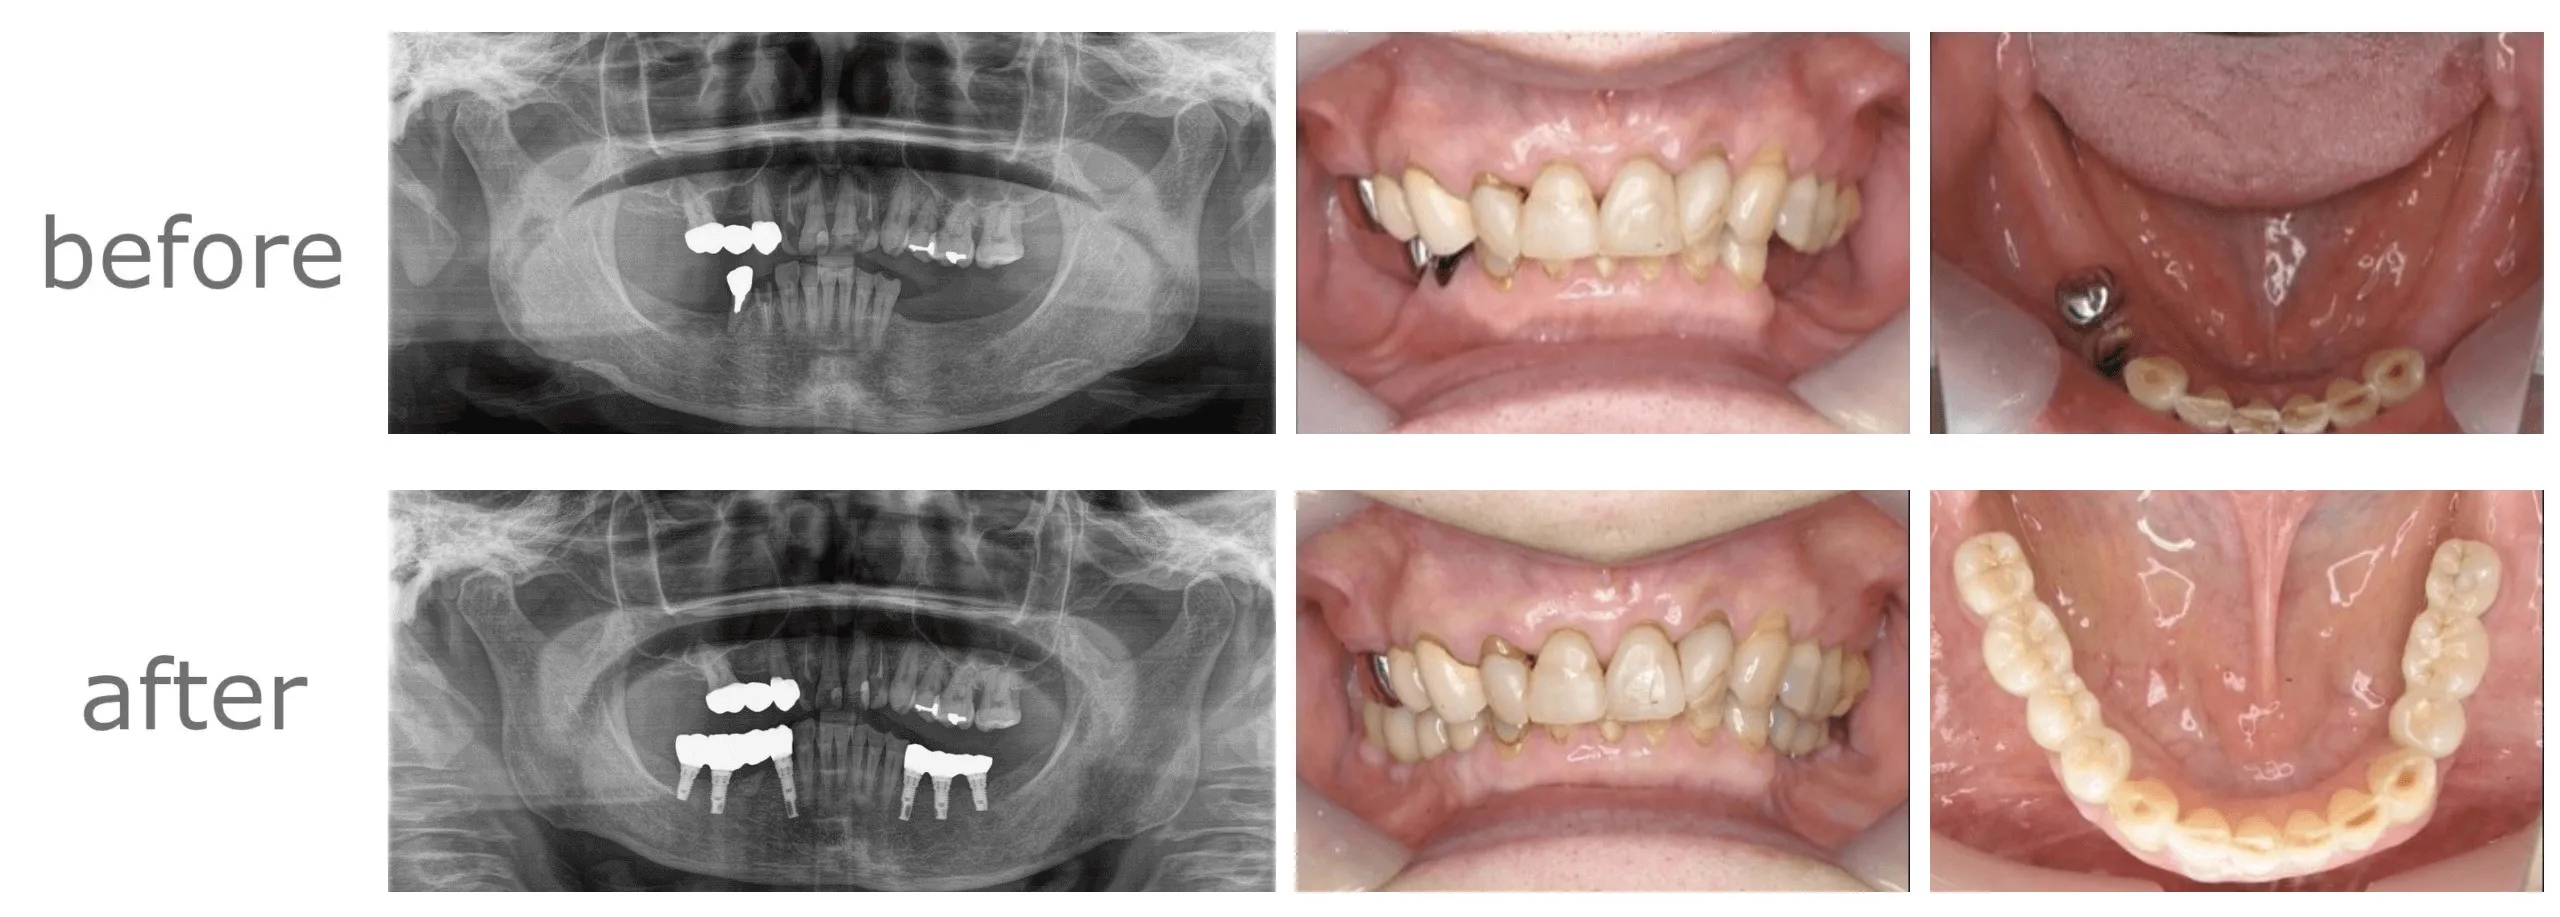

症例CASE

症例①

【年齢・性別】 50代・女性

【主訴】 左上3が歯根破折しているといわれ残せないと言われた。

インプラントを考えている 右下奥歯は欠損して10年以上経つ、インプラントするか迷っている

【期間】 2年半

【通院回数】 11回

【費用】 1,188,000円